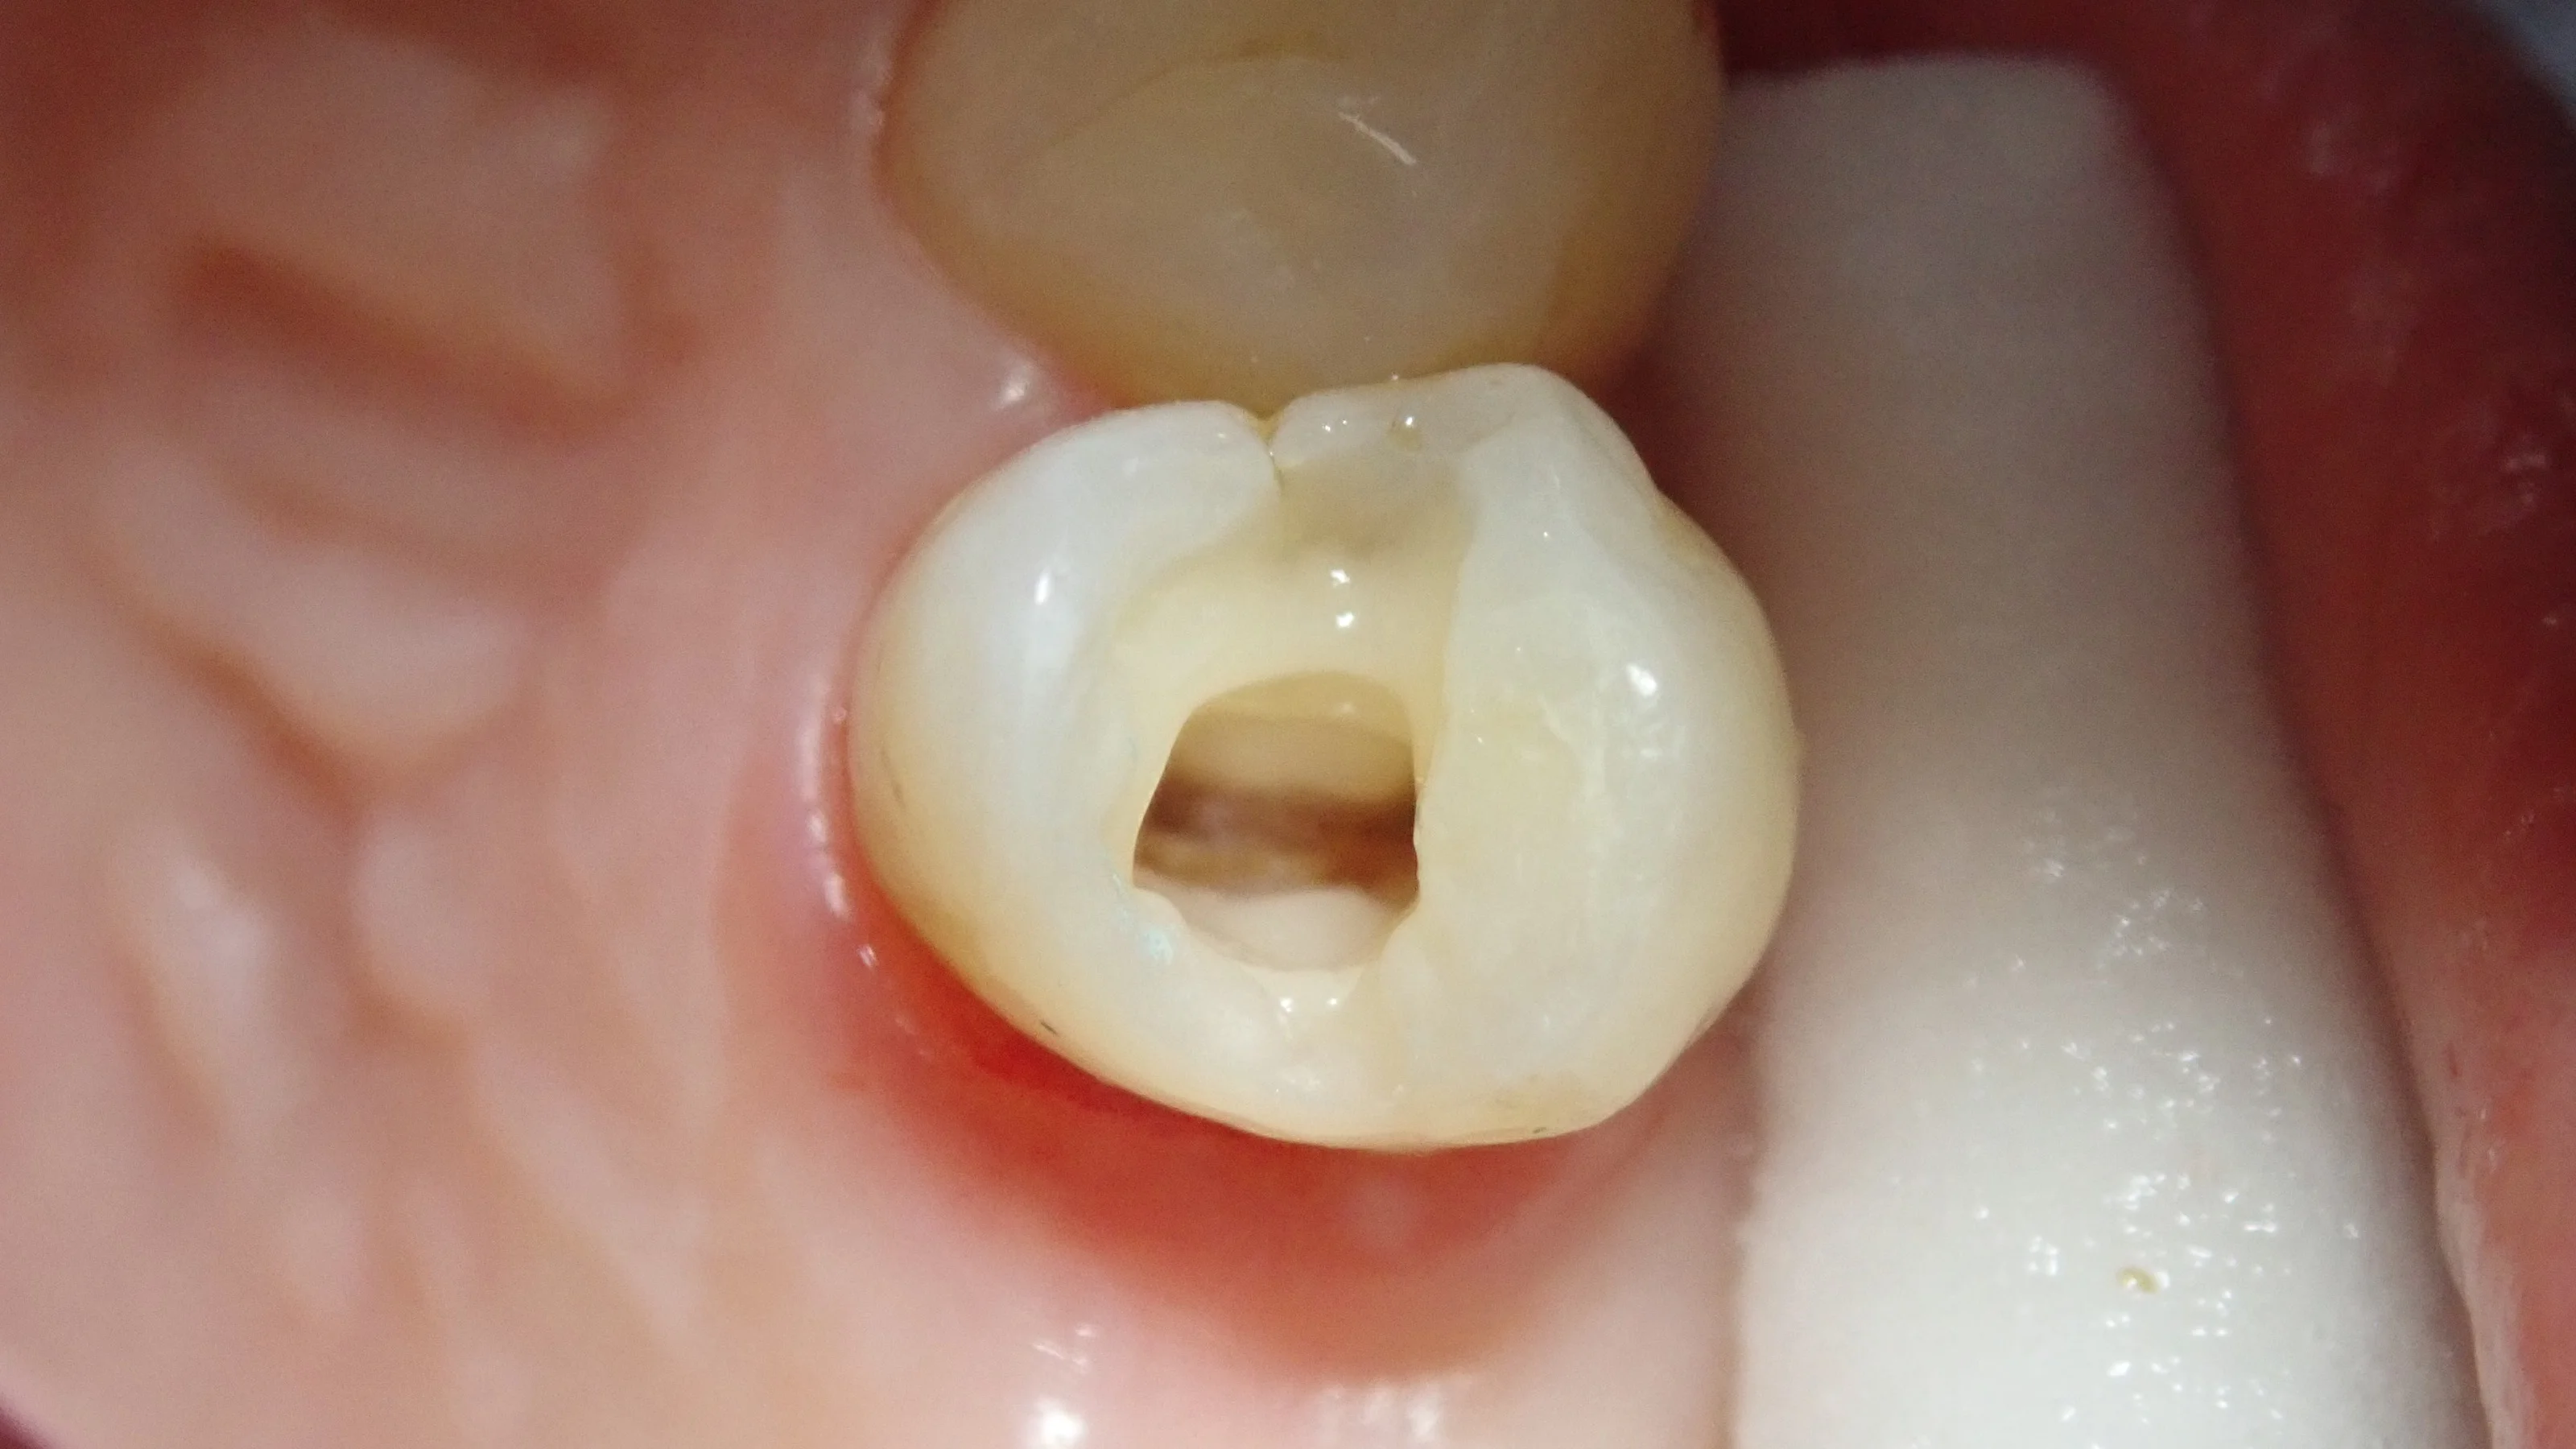

虫歯を取り切った状態がこちら。

・・・案の定、虫歯が神経まで行ってしまっていました。

神経が生きていれば、露出した段階で出血してきますが・・・神経のあるはずの場所を触ってみても全く出血せず。

確実に神経が死んでおり、神経の治療が必要である旨を説明し、同意を得たので、神経の治療へ。

この写真の歯の中央に見えているのが最終的な詰め物です。

ガッタパーチャポイントという柔らかいゴムのようなものを使います。